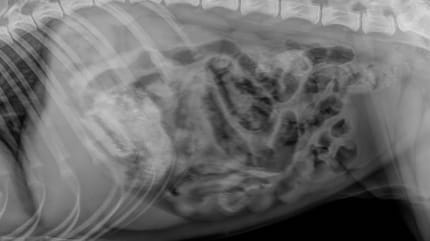

¿Qué encontraron en la radiografía?

La radiografía en la clínica veterinaria reveló el terrible "tentempié"

Dentro de la albóndiga se escondía una cuchilla de afeitar, tal y como reveló más tarde la radiografía.